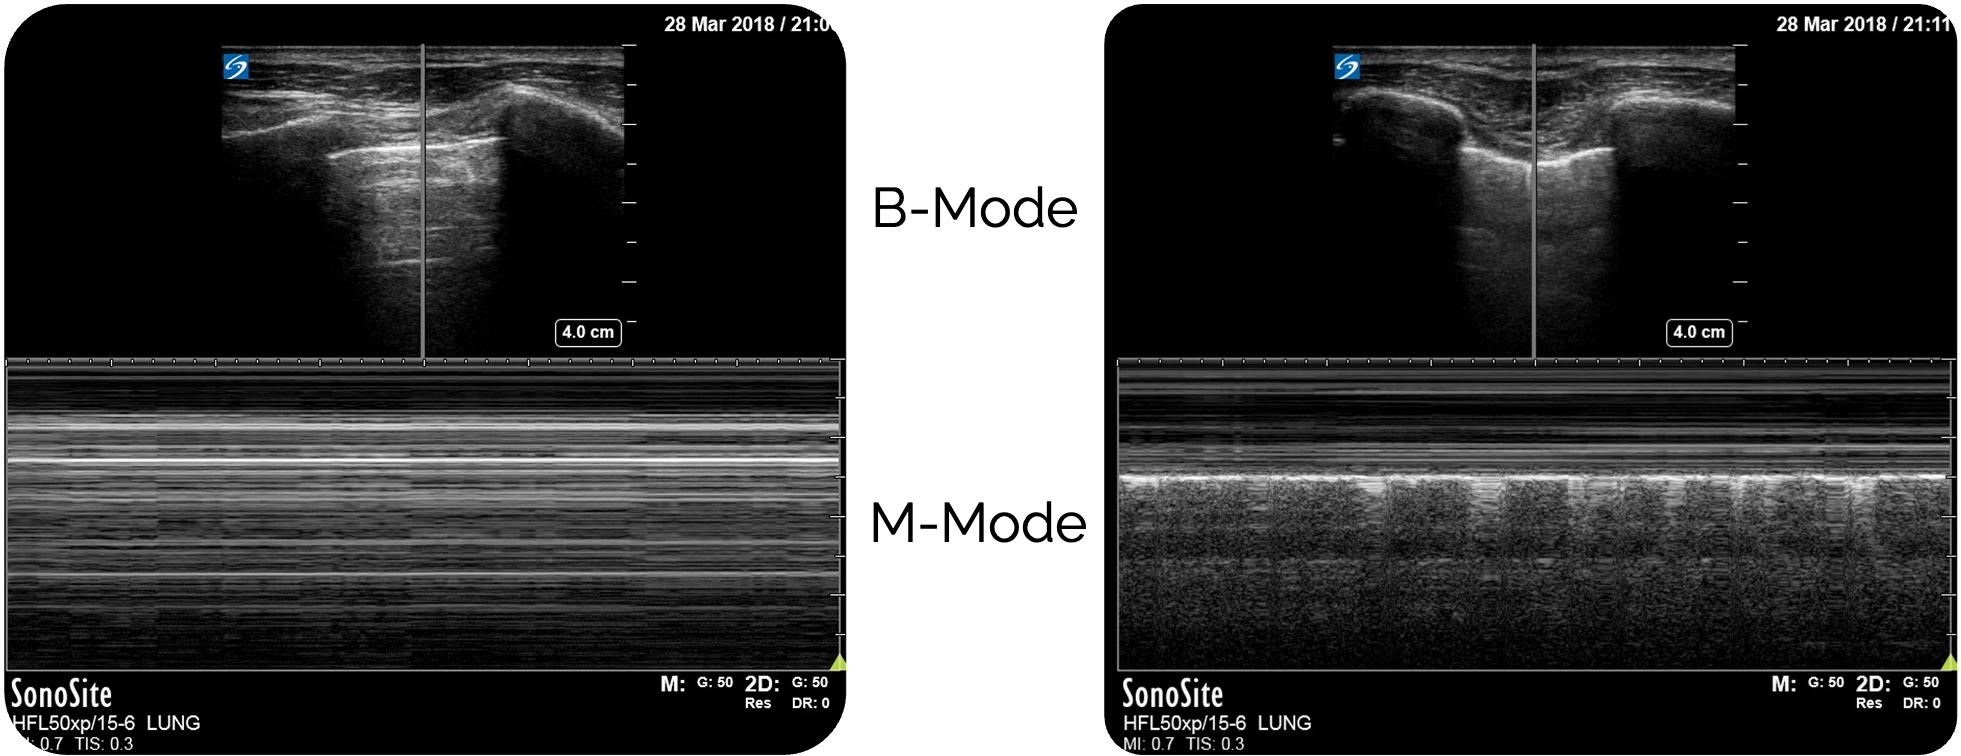

- Seashore-Sign (M-Mode

): ruhige Linien oben (unbewegliche Thoraxwand) (blauer Pfeil) und körnige Struktur (bewegende Lunge ) unten (roter Pfeil)

Pathologische Zeichen (Pneumothorax -verdächtig):

- Barcode-Sign (M-Mode

): nur horizontale Linien (roter Pfeil)

Pneumothorax im M-Mode :

Im M-Mode

Statt des Seashore-Zeichens zeigt sich ein homogenes, horizontal gestreiftes Muster über das gesamte Bild – das sogenannte Barcode- oder Stratosphären-Zeichen.

Dieses Muster weist auf einen fehlenden pleuralen Kontakt hin und ist damit hochverdächtig auf einen Pneumothorax

Figure 5 (links) und Figure 3 (rechts) aus Ketelaars, Rein., Reijnders, G., van Geffen, GJ. et al. ABCDE of prehospital ultrasonography: a narrative review. Crit Ultrasound J 10, 17 (2018). https://doi.org/10.1186/s13089-018-0099-y. Teilausschnitt des Originalbilds. Es wurden die Beschriftungen ergänzt.

Rechts: Normalbefund der Pleura im M-Mode